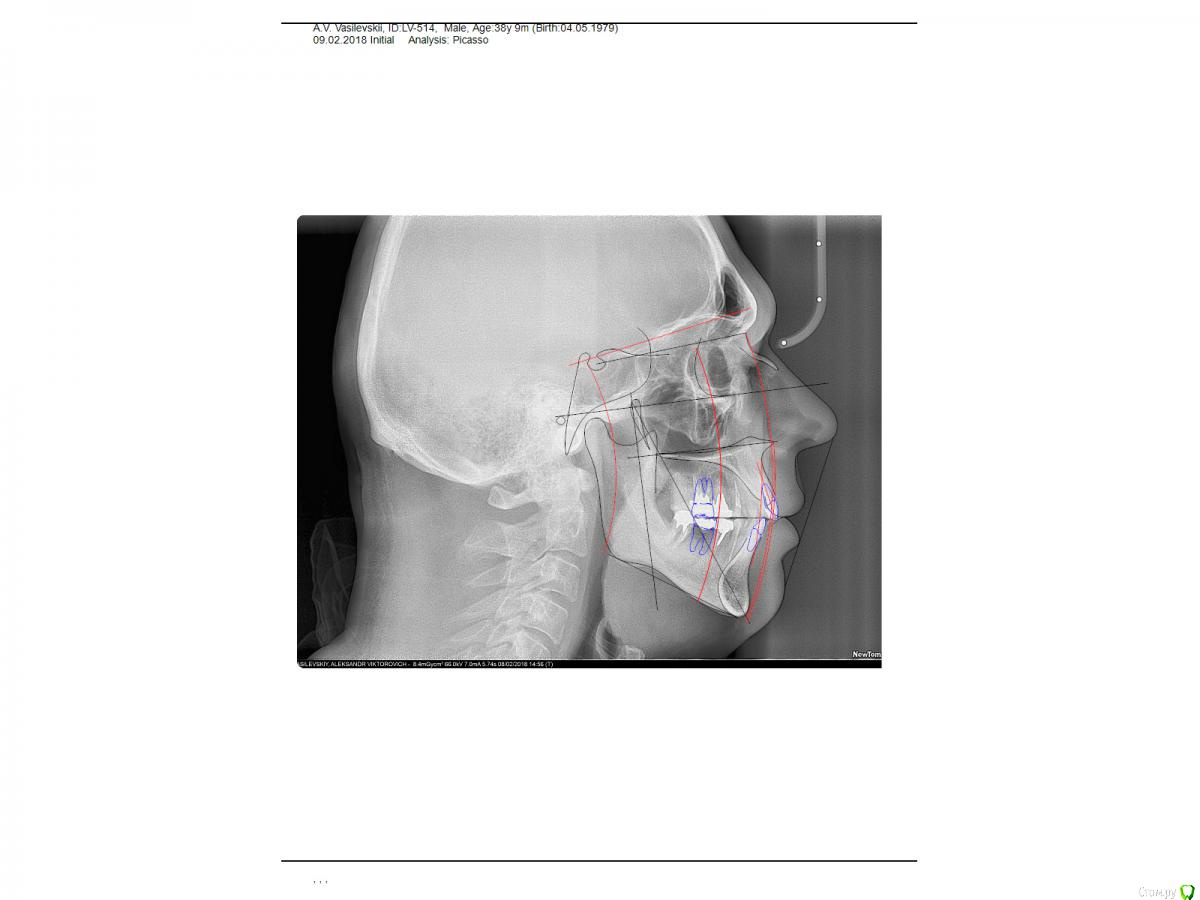

Taurus007 Опубликовано 9 февраля, 2018 Поделиться Опубликовано 9 февраля, 2018 После очных консультаций в разных клиниках (Москва) выяснилось много вариантов, что несколько смущает. Рекомендации и планы лечений такие:1.Удалить 15,16.25,26,37,47 . С учетом ранее удаленных 2х нижних шестерок, поставить 8 имплантов.При необходимости - подсадка костной ткани.2.Удалить 46,47,36,37,16,26, на их место импланты. 15,25 - поменять коронки. Дополнительно: а. Синус-лифтинг в различных комбинациях, либо без него. Мнения разные. б. Высказано мнение, что необходима коррекция прикуса, поскольку если его не трогать, а начать установку имплантов, то нагрузка на них будет чрезмерной, что повлечет рассасывание кости со всеми вытекающими. Сделал ТРГ, пока только снимок, анализ и расчет ТРГ на след. неделе будет готов. Из истории зубов: коронки стоят 9 лет, 35й - 1 год. Ссылки на ТРГ и компьютерную томографию . Сам я изначально склонялся к первому варианту. Без исправления прикуса.Подскажите, как все-таки лучше поступить? Важные вопросы: насколько необходимо исправление прикуса, и нужен ли синус-лифтинг, судя по КТ? Ссылка на комментарий

Taurus007 Опубликовано 13 февраля, 2018 Автор Поделиться Опубликовано 13 февраля, 2018 wladdXОгромное спасибо за скриншоты. Я бы даже близко так не смог) Пришел расчет и анализ ТРГ. Заключение.pdf Ссылка на комментарий